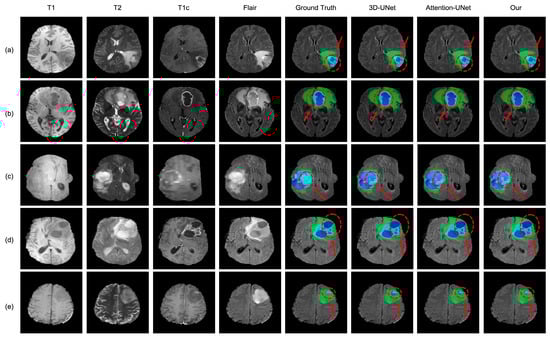

4.3. Analysis of the Bad Tumor Segmentation Results

| Cases | DSC | |||

|---|---|---|---|---|

| ET | TC | WT | AVG | |

| (a) BraTS2021_00493 | 0.885 | 0.924 | 0.270 | 0.693 |

| (b) BraTS2021_00494 | 0.964 | 0.990 | 0.730 | 0.895 |

| (c) BraTS2021_01666 | 0 | 0.738 | 0.916 | 0.551 |

| (d) BraTS2021_01179 | 1.000 | 0 | 0.769 | 0.590 |

| (e) BraTS2021_01293 | 0.541 | 0.929 | 0.874 | 0.781 |